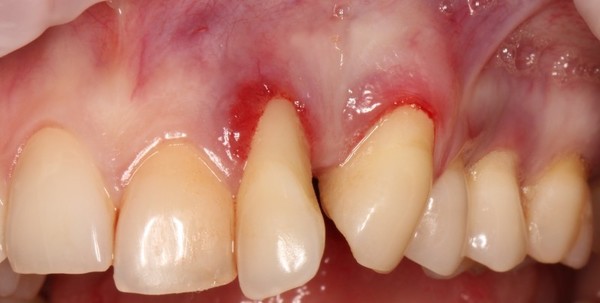

Абсцедирующий

Характеризуется появлением гнойного очага, то есть абсцесса. Эта форма пародонтита способна привести к атрофированию костной ткани.

Фото 3. Абсцедирующий пародонтит. В области коренных зубов наблюдается гнойный абсцесс и сильная припухлость.

Симптомы заболевания: кровоточивость десен, углубление пародонтального кармана до четырех миллиметров, подвижность зубов, возникновение болевых ощущений даже в состоянии покоя, появление гнойных мешочков.

Причины возникновения заболевания — зубной налет и камень, а также запущенный гингивит и другие патологии функционирования организма.

Чаще всего пораженный зуб удаляют, но в некоторых ситуациях возможно лечение без операции.